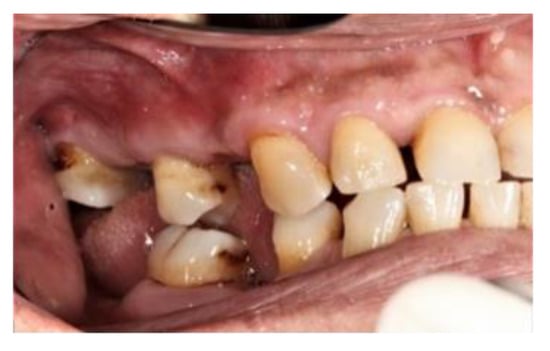

2. Case Report

The subject involved in this clinical study was a healthy woman, 54 years old. The request of this patient was to improve her mouth both functionally and aesthetically, which was altered because of the partial edentulism (Kennedy Class II). She asked to avoid any invasive surgery. During the anamnesis, she declared not to be affected by any systemic pathology (e.g., diabetes, hypercholesterolemia or hypertension). She also declared not to be affected by an allergy to any medication or similar drugs; she declared not to be subjected to any pharmacologic treatment except some analgesic therapy to treat sporadic headaches. The patient claimed to smoke 20 cigarettes a day for more than 20 years. The next step was to perform an objective examination, associated with a series of intraoral pictures (Figure 1, Figure 2, Figure 3, Figure 4 and Figure 5) and to the analysis of a radiographic exam (orthopantomography, Figure 6) that was acquired 10 months earlier when the same subject underwent the therapy and the teeth extraction 4.7–4.8. The objective examination showed poor oral hygiene, with plaque accumulation as well as the presence of many pigmentations due to excessive smoking. The radiography showed bilateral bone atrophy together with periodontal damage for most of the residual dental elements. These conditions represented a limitation to the insertion of implants for a fixed prosthesis.

Figure 2. Right lateral view.

Prosthesis 03 00038 g002

Figure 3. Left lateral view.

Prosthesis 03 00038 g003